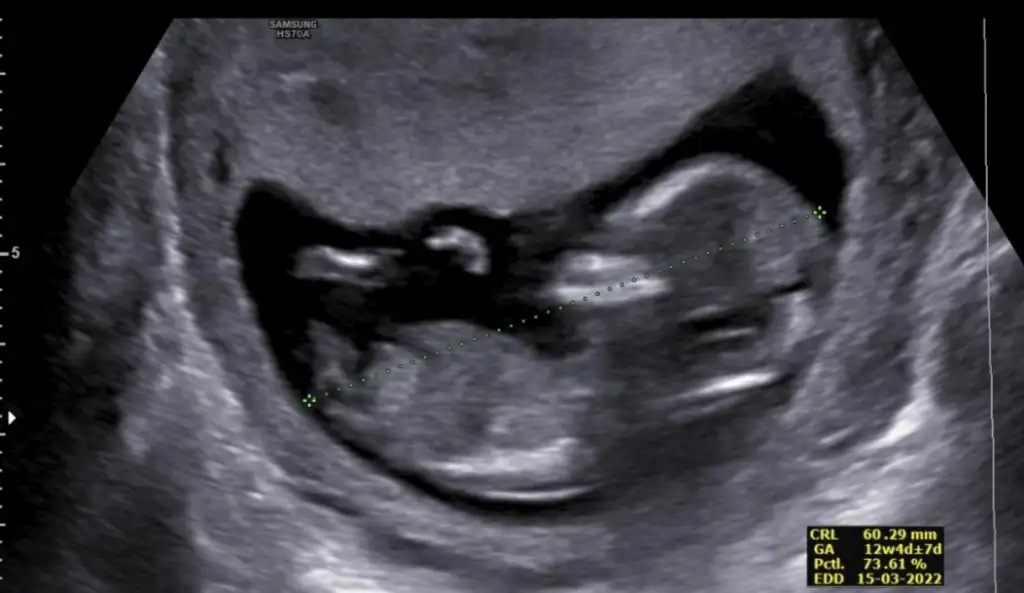

Emin olamadim kız gibi sankiBizde bugün kontrolden çıktık 12+3 haftalığız ,doktor cinsiyet için emin olamadı resimlerden siz yorum yapabilirmisinizIkra meyra

Doktorda bir kız bi erkek dedi bakalım 3 hafta sonra kontrol var gösterir ozaman inşEmin olamadim kız gibi sanki

Kız gibiKizlar bu da benim yavrum 12+3 sizce nedir çok merak ediyorumEki Görüntüle 2910088